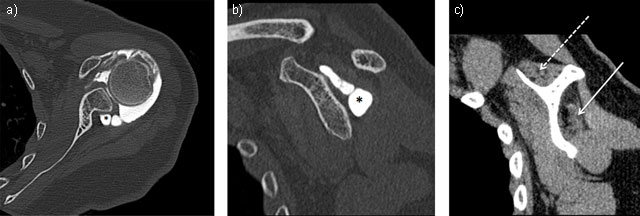

Figure 3

Neuropathy of suprascapular nerve by voluminous labral cyst (star) sited in spinoglenoid notch extending to supraspinatus fossa inducing a severe atrophy and fatty degeneration of infraspinatus (solid arrow) whereas the supraspinatus muscle is less involved (dashed arrow). Axial (3a = FIGURE 7 uploaded online manuscript) – sagittal (3b = FIGURE 8 uploaded online manuscript – 3c = FIGURE 9 uploaded online manuscript) CT Arthrography.